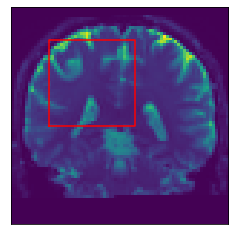

Inference stage. Now we present results of the inference stage with two DW-MRI real datasets. First, the free access dataset Stanford HARDI (Rokem et al., 2015) included in DIPY Library, with dimension (81,106,76) voxels and 160 signals per voxel (number of gradients). The acquisition protocol composed uses 150150150 gradients with b-value equal 200020002000 and 101010 with b-value equal zero. Second, a local DW-MRI with (128,128,70)12812870\left(128,128,70\right) voxels with 646464 gradients with b-value 100010001000 plus 111 gradient with b-value 00, each of them is repeated 555 times resulting in signals of size 325325325. Training time for our models by depends on datasets: The Voxel model takes 1.24sec.1.24𝑠𝑒𝑐1.24sec. for the Stanford HARDI and 1.24sec.1.24𝑠𝑒𝑐1.24sec. for out local dataset. Meanwhile, Neighborhood model takes 1.91sec.1.91𝑠𝑒𝑐1.91sec. for the Stanford HARDI and 3.34sec.3.34𝑠𝑒𝑐3.34sec. for our local dataset. Prediction times are shown in Table 1. Figure 7 compares the final results in a Stanford dataset slice, showing the local detected structure with the studied models. More slices results are presented in Appendix C.

(a) DW-MRI

(b) Slice Zoom

(c) NNLS

(d) CSD

(e) VOX

(f) NBH

Figure 7: Predicted intravoxel structure in real data with the compared models.